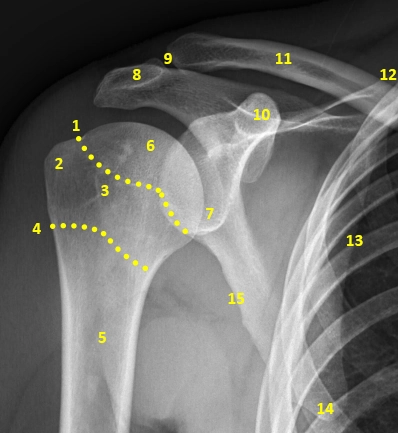

X Quang khớp vai